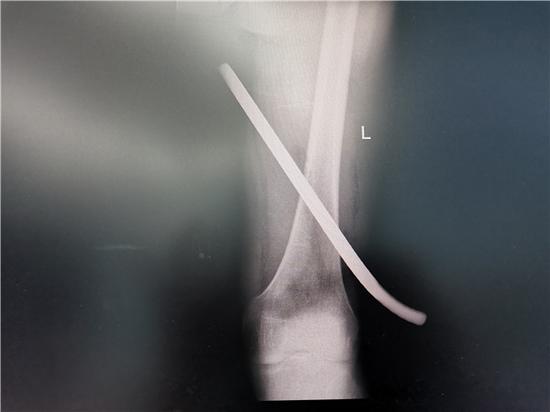

10 月 24 日 10 时许,农民工王先生在工地施工时因浇筑模板倒塌,从 1 米余高的地方不慎坠落,被地面约 18 号螺纹钢刺穿左大腿,钢筋从腘窝部刺入,从大腿内侧穿出,现场在众多工友的帮助下,将体外大段钢筋予以截除后,送往就医,到达当地医院后被告知因钢筋贯通部位特殊,入口和出口都毗邻下肢重要血管神经,需要转上级医院治疗。

辗转几家医院后,王先生于 17 时 16 分被送到湖南省第二人民医院,手足外科值班医生舒子震医师也惊呆了,只见一根满是锈渍的钢筋贯穿了王先生的左侧大腿,血液渗出,舒医生立即检查病人病情,发现钢筋从患者左侧腘窝部刺入,由下向上,从大腿根部穿出,钢筋两端在体表可见,还有约 30 厘米存留在大腿内,油渍铁锈污染严重。

李奇伟主任医师术后表示,钢筋从腓总神经表面刺入,毗邻腘动静脉,从坐骨神经深处贯通至大腿根部,钢筋上有大量的铁锈、油渍、泥沙,术中进行彻底清创并反复冲洗,不能有一丝遗漏,不然很难避免感染等并发症的发生。